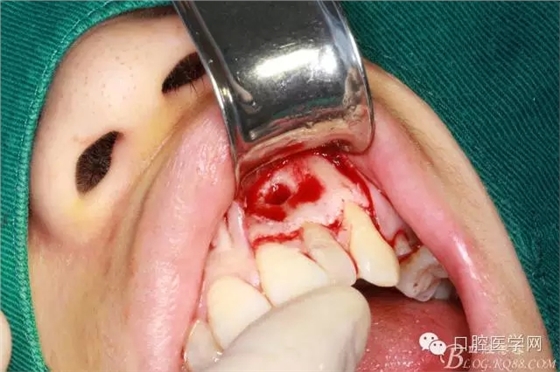

翻全厚瓣后暴露骨面

確定根長(根管充填時已確定)

去 骨

可見囊腫